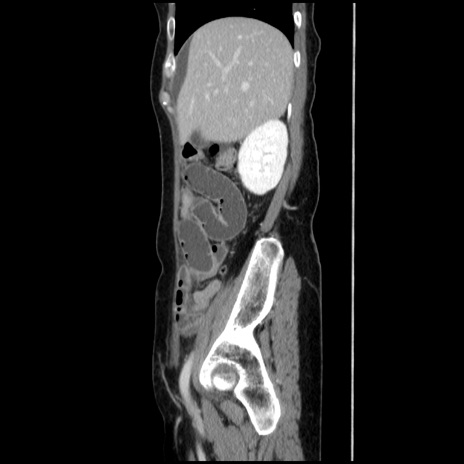

冠状断像

【症例】40歳代 女性

【主訴】上腹部痛、嘔気・嘔吐

【現病歴】約9時間前頃から急に上腹部痛、嘔気、嘔吐が出現。改善しないため救急要請。

【既往歴】子宮頚癌(広汎子宮全摘術、放射線療法)、腸閉塞

【身体所見】腹部:平坦、軟、腸雑音亢進、上腹部を中心に腹部全体に圧痛あり。

【データ】WBC 8400、CRP 0.03